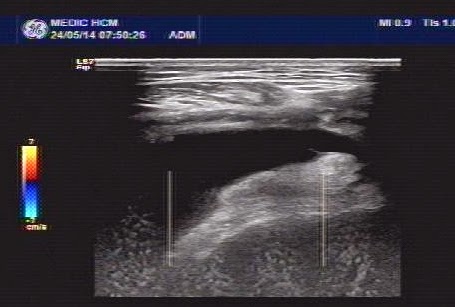

Ultrasound first scanned at the right knee, detecting swelling of the suprapatella recessus with homogeneous fluid (2 ultrasound pictures).

For make sure the diagnosis: puncture of the knee joint with ultrasound guided..removing the yellowish synovial fluid.